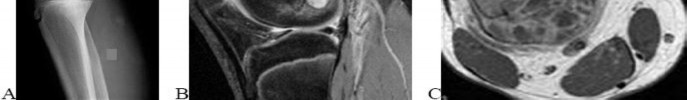

A 15-year-old male presents with deep knee pain awakening him at night. Radiographs show a permeative destructive lesion in the distal femoral metaphysis with a 'sunburst' periosteal reaction and Codman's triangle.

Biopsy confirms high-grade conventional osteosarcoma. What is the most critical prognostic factor for long-term overall survival in this patient?

Explanation

For localized high-grade osteosarcoma, the most important prognostic indicator is the histologic response to neoadjuvant chemotherapy. This is evaluated during the definitive resection. A 'good response' is typically defined as greater than 90% or 99% tumor necrosis. Patients who achieve this level of necrosis have a significantly improved disease-free and overall survival rate compared to 'poor responders' who have extensive viable tumor cells remaining.